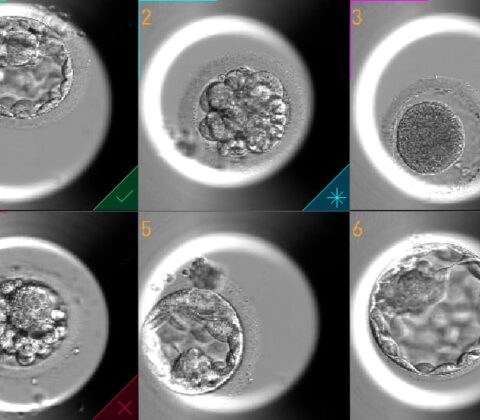

desenvolvimento embrionário